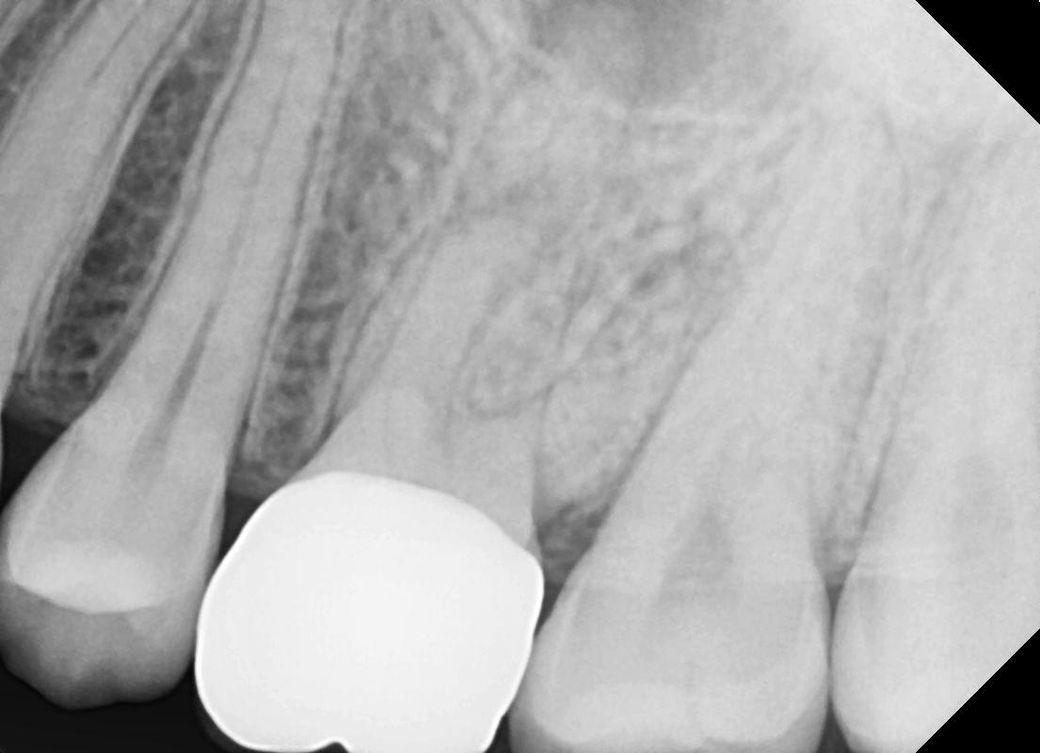

• 2번 째 사진

네 치근단 염증이 있는 상태가 엑스레이 상에서도 확인이 됩니다 크라운 뜯거나 구멍을 내고 신경치료 시도하면 됩니다